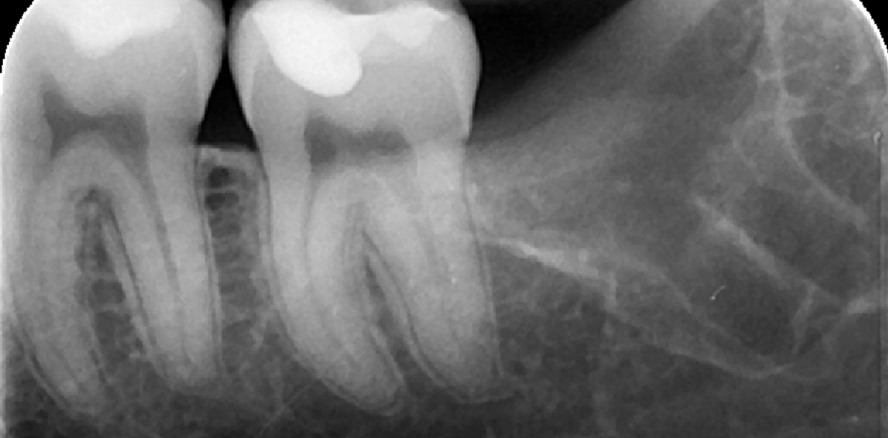

Eine 22 Jahre alte Patientin, bei guter Gesundheit, suchte die Klinik der Autoren in Via San Gottardo 83, Monza (Italien), auf und berichtet über Schmerzen vom 38 ausgehend und sich über den gesamten unteren Bogen ausbreitend. Die erste Panoramaabbildung zeigt die Kompression des Nervus mandibularis, der die unteren Wurzeln des 38 berührt – eine physikalische Inklusion der Schleimhaut und partielle Knocheninklusion in engem Zusammenhang mit dem Nervus alveolaris inferior. Die körperliche Untersuchung zeigt ödematöse und erythematöse Schleimhaut distal zu Element 37. Keine Änderung der Sensibilität im betroffenen Zahnbogen. Eine zweite Röntgenaufnahme mithilfe eines Dentalscans zeigt die Lage das Nervus alveolaris inferior an der distolingualen Spitze, wie im CT bestätigt.